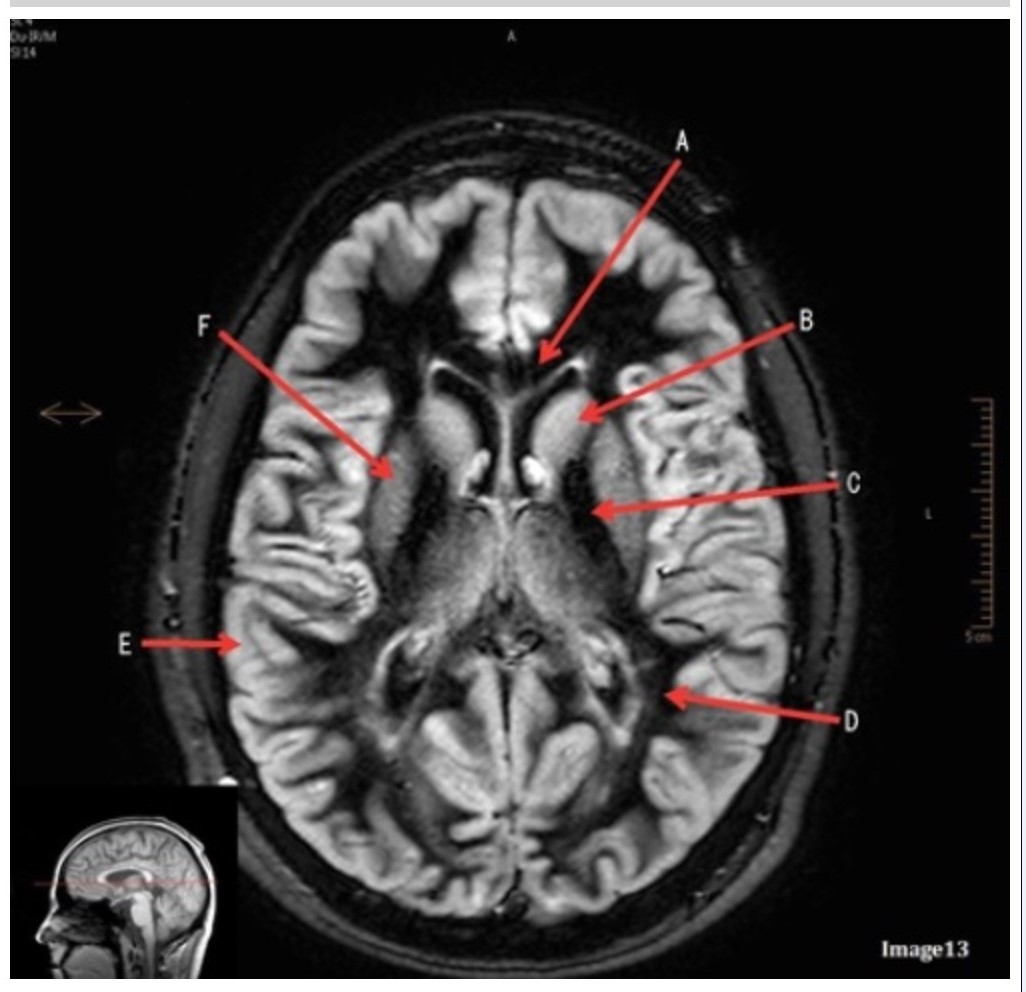

Letter E in Image 13 is pointing to:

A. Grey matter

B. White matter

C. Lentiform nucleus

D. Caudate nucleus

E. Internal capsule

Letter B in Image 13 is pointing to:

A. Splenium of the corpus callosum

B. Genu of the corpus callosum

C. Lentiform nucleus

D. Caudate nucleus

E. Internal capsule

Letter F in Image 13 is pointing to:

A. Grey matter

B. White matter

C. Lentiform nucleus

D. Caudate nucleus

E. Internal capsule

Letter D in Image 13 is pointing to:

A. Grey matter

B. White matter

C. Lentiform nucleus

D. Caudate nucleus

E. Internal capsule

Letter C in Image 13 is pointing to:

A. Splenium of the corpus callosum

B. Genu of the corpus callosum

C. Lentiform nucleus

D. Caudate nucleus

E. Internal capsule